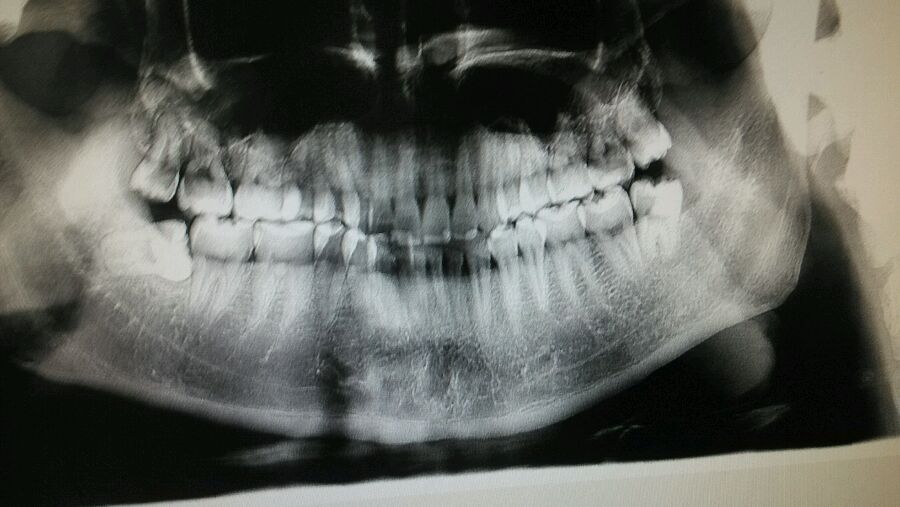

下面两颗以拔 上面两颗从来没有疼过要拔吗?

我觉得除了右下那颗,其他都挺正常滴啊